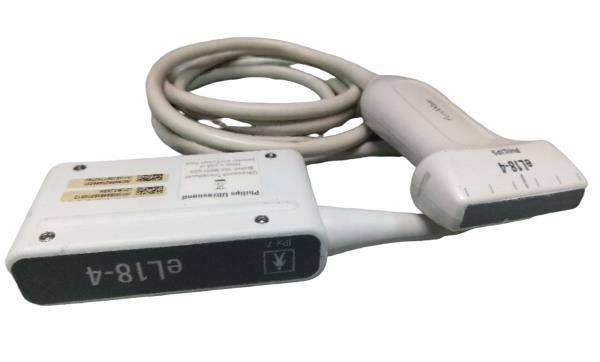

Probe Function: 3.5MHZ convex, abdominal organs